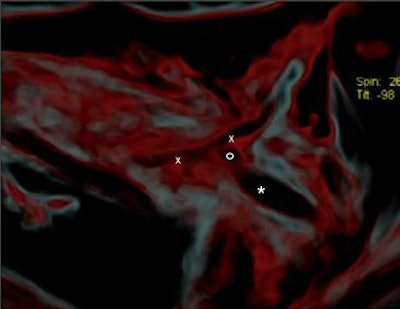

Using MDCT, the researchers were able to identify the subclavian artery with its higher density (-40 HU), compared to the surrounding soft tissue (-290 HU), and found damage to the left dorsal artery wall that was 13 mm in length. Also visible was a 3-mm irregular pseudoaneurysm, which they noted was a typical complication of a subclavian artery laceration. A large hematoma was seen in the surrounding soft tissue, and the arrowhead (+1840 HU) was found in situ 6.5 mm away in the dorsocranial direction, they added.

![]() |

| CT image shows the injury (x-x) and the head of the arrow (*). Figure published in: JArcheol Sci, in press, Pernter P., Gostner P., Egarter Vigl E., Rühli, F. J., "Radiologic proof for the Iceman's cause of death (ca 5300 BP), Copyright Elsevier. Image courtesy of Dr. Frank Rühli and the University of Zurich, Switzerland. |

"It seems most likely that (the arrowhead) lacerated the subclavian artery. By removing the shaft of the arrow perimortem, its head must have been slightly retracted to the actual position where the barbs caught in the tissue and, eventually, the arrowhead separated from the now missing shaft," the group wrote. "In the surrounding soft tissue one can see linear air incorporations as well as multiple irregular partially confluent densities (-80 HU), with the latter likely representing a hematoma. It spreads dorsocaudally between the ribs and the scapula, and also into the shooting channel toward the subcutaneous soft tissues" (Journal of Archaeological Science, March 15, 2007).